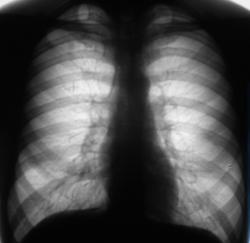

Флюорограмма 2007 год.

Флюорограмма 2008 г.

Флюорограмма 2009 г.

В 2008 году пациент был взят на контроль и был вызван на дообследование, но "вдруг исчез" из населенного пункта. Но в этом году, а именно сегодня пациента удалось дообследовать.

Че ту долго думать Суперрр раскручивать надо, на первом месте туберкулез, конечно.

Инфильтративный туберкулёз справа

инфильтративный туберкулёз.